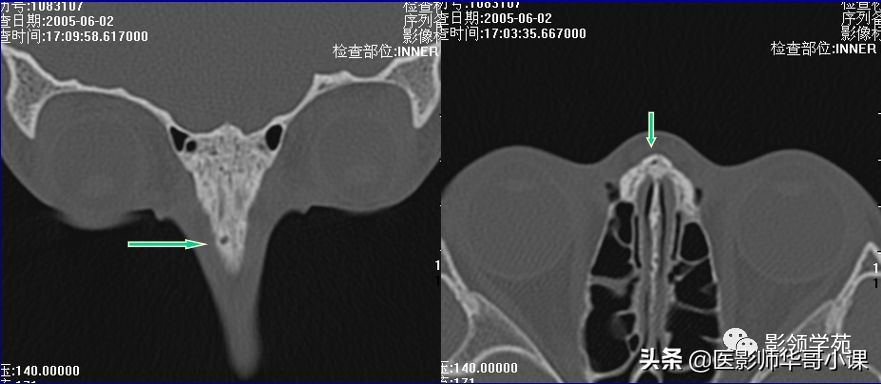

鉴别诊断

- 鼻缝

- 鼻骨孔

- 缝间骨

鼻颌缝

鼻额缝

额颌缝

鼻骨间缝

鼻骨孔

缝间骨